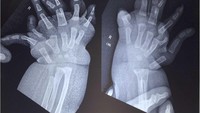

Selain itu, rontgen tangan menunjukkan duplikasi tipe III pada jari tengah, duplikasi tipe V pada jari manis, jari kelingking yang mengalami deviasi ulnar, serta pergelangan tangan dengan tiga tulang. Sementara itu, anggota gerak atas kiri, wajah, tulang belakang, panggul, dan ekstremitas bawah tampak normal. Pasien tidak mengalami obesitas, dan hasil parameter darah berada dalam batas normal.Foto: jurnal PlumX Metrics